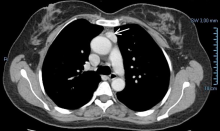

[3]Figure 1. (A) Chest CT showing a tumor measuring 24 x 12 mm in the anterior mediastinum, suggestive of a small thymoma. The tumor showed a high contrast enhancement. There is a clear plane between the mass and the aorta and no compression of any mediastinal structures. (B) No connection with the cervical thyroid was observed. In retrospect, this is one of the features of mediastinal ectopic thyroid.

A 58-year-old woman sought medical treatment because of abdominal pain. Previously, she had been diagnosed with colonic diverticular disease. At the emergency department, an abdominal computed tomography (CT) was performed and no abdominal abnormality was seen. A 6 mm pulmonary nodule was detected in the left inferior lobe and a follow-up chest CT revealed an anterior mediastinum density below the level of the aortic arch, measuring 24 x 12 mm and showing high contrast enhancement (Figure 1). Lymphadenopathy, thymoma, ectopic thyroid, and parathyroid adenoma were the diagnostic hypotheses in the radiology department.